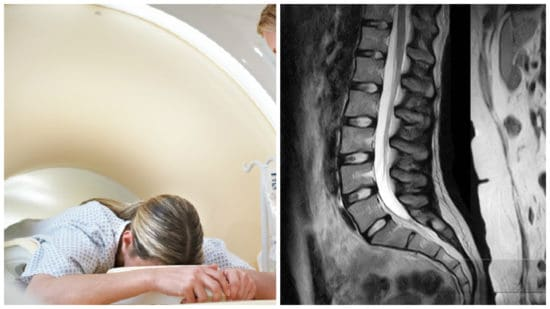

5 реальных причин боли в пояснице при “чистом” МРТ

🔥 МРТ чистое, а боль есть: 5 причин, о которых вам не сказали

❗ Почему МРТ не показывает причину боли

МРТ — это картинка структуры: кости, диски, ткани.

Но оно почти не показывает:

• как двигается тело

• как работают мышцы

• где перегрузка

👉 А боль чаще возникает не из-за “поломки”, а из-за неправильной работы системы.